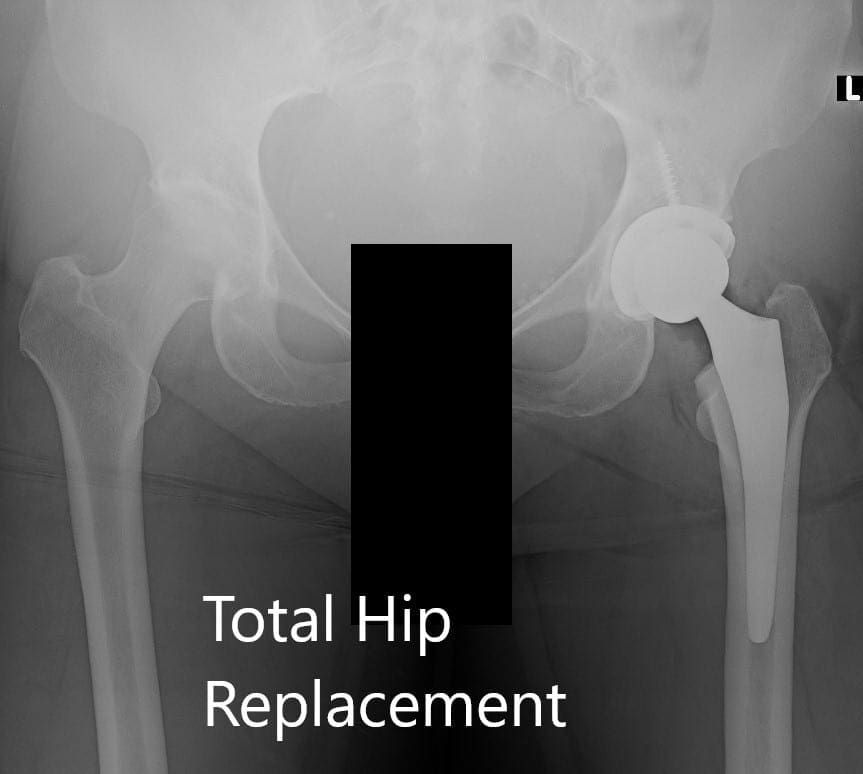

Implant used: Acetabular shell 60 mm with a 6.5 mm x 30 mm cancellous screw, with ceramic femoral head 36 mm, 0-degree polyethylene with 127-degree neck angle hip stem.

Postoperative X-ray of the pelvis showing AP and lateral views